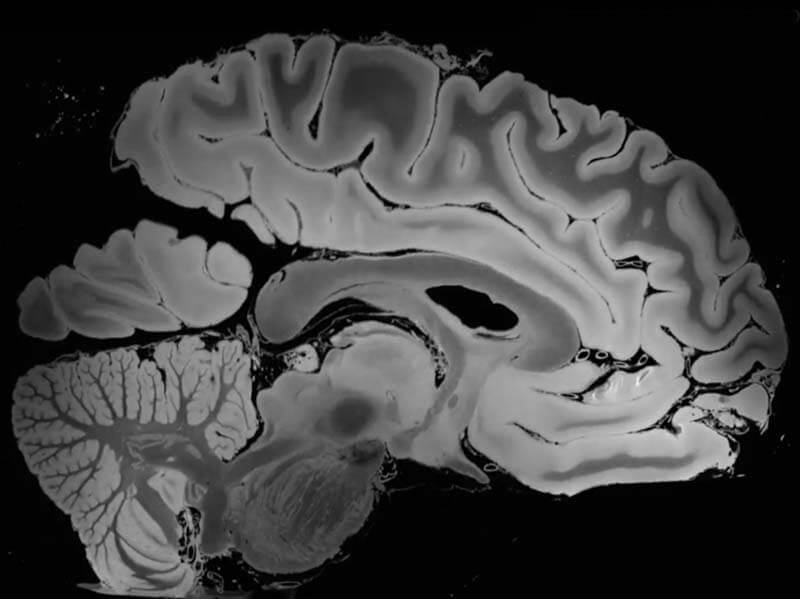

Количество исследований, посвященных ключевым и практическим аспектам МРТ мозга, в последнее время стремительно растет (особенно за границей), подробнее https://centrmrt.spb.ru/mrt/mrt-golovy/mrt-golovnogo-mozga. Развитие надлежащих технологий является ключом к открытию сразу нескольких перспективных направлений. Например, возникла возможность следить за особенностями циркуляции крови в мозговом сегменте, который находится в состоянии активации – она может быть использована при выявлении нарушения мозгового кровообращения (инсульта) или при подборе некоторых сосудистых препаратов.